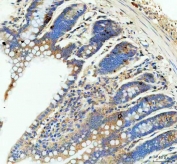

GIP antibody is widely used in endocrinology, metabolism, and diabetes research. It is suitable for immunohistochemistry, ELISA, and western blotting to detect GIP peptide expression in intestinal tissue, pancreas, and circulation. This antibody supports studies of incretin biology, glucose regulation, and hormone secretion. In translational research, it aids in characterizing the mechanisms of incretin-based therapies and their metabolic outcomes. GIP detection is also employed in assessing enteroendocrine cell distribution and functional activation.